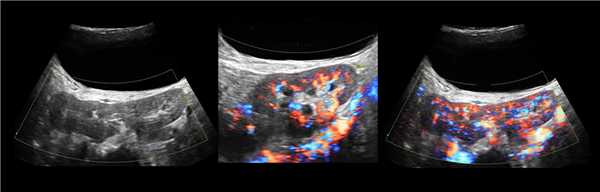

Рисунок. Двустороннее уретероцеле на УЗИ: в режиме ЦДК из верхушек уретероцеле определяется выброс мочи.